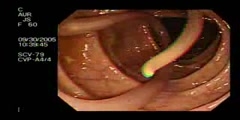

Worm Insertion

Worm Insertion